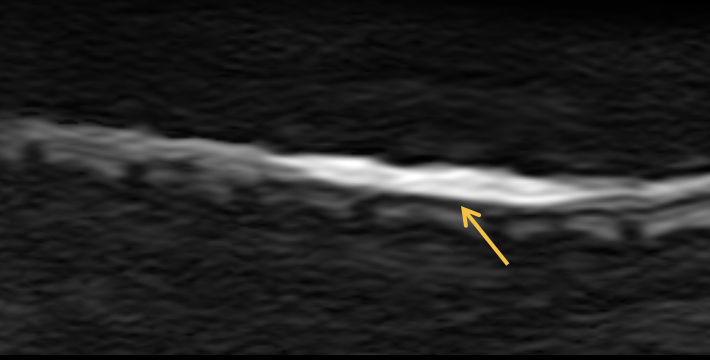

향상된 확산강조영상(Diffusion weighted imaging) 을 이용한 미세 뇌 손상 정밀 평가

확산강조영상에도 AI 기술이 적용되어 이전보다 향상된 확산강조영상을 제공합니다.

이전에 확인하기 어려웠던 척수 실질에 대한 확산강조영상 정밀 평가 및 미세 뇌 실질 병변을 정밀하게 평가합니다.

척수 경색 / 척수 종양 / 척수연화증

척수 실질 경색성 변화

DWI(상)/ ADC(하)